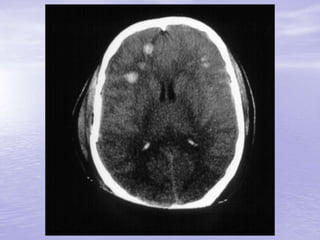

•LESÃO FOCAL

CONTUSÕES

• Única ou múltiplas

• Concussão

• Área de impacto ou

contragolpe.

– Manifestações

dependem da área

lesada

– Lesões golpe-

contragolpe

principalmente frontal e

occipital

– 20 % evoluem para

hematomas cirúrgicos